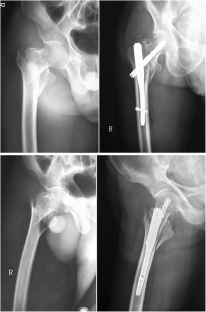

Fig. 2